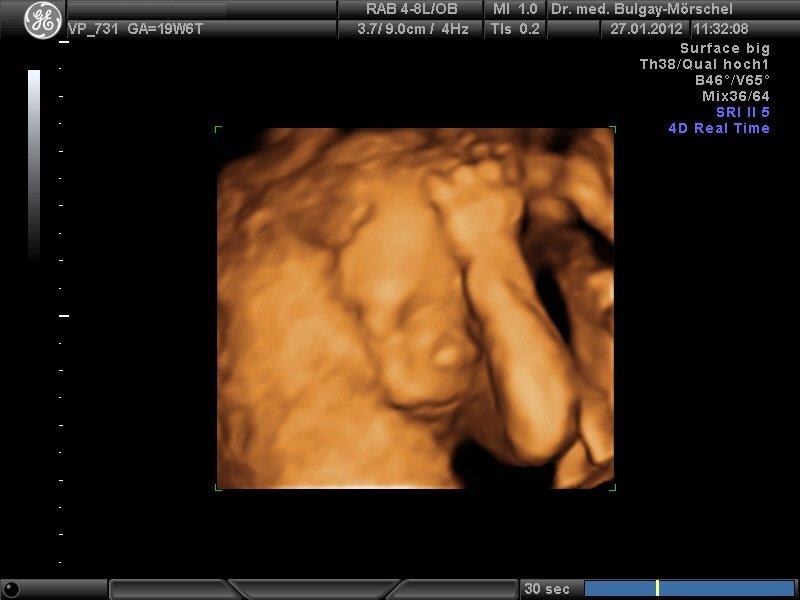

Die 3D/4D Sonografie ermöglicht die dreidimensionale Darstellung des Feten. Die „Live 3D-Untersuchung“ mit bewegten Bildern wird als 4D bezeichnet. Diese Techniken sind als ergänzende Untersuchungsmethode zur 2D-Sonografie zu verstehen.